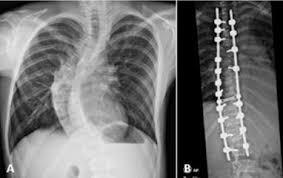

A Case Report Of A 13 Year Old Girl Diagnosed With Superior Mesenteric Artery Syndrome After Undergoing Spine Correction With Posterior Fusion For Rapidly Progressed Juvenile Idiopathic Scoliosis Sciencedirect

Superior Mesenteric Artery Syndrome As A Complication Of Scoliosis Surgery Mdedge Surgery

Acute Onset Of Superior Mesenteric Artery Syndrome Following Surgical Correction Of Scoliosis Case Report And Review Of Literature Sciencedirect

Superior Mesenteric Artery Syndrome Following Scoliosis Surgery Its